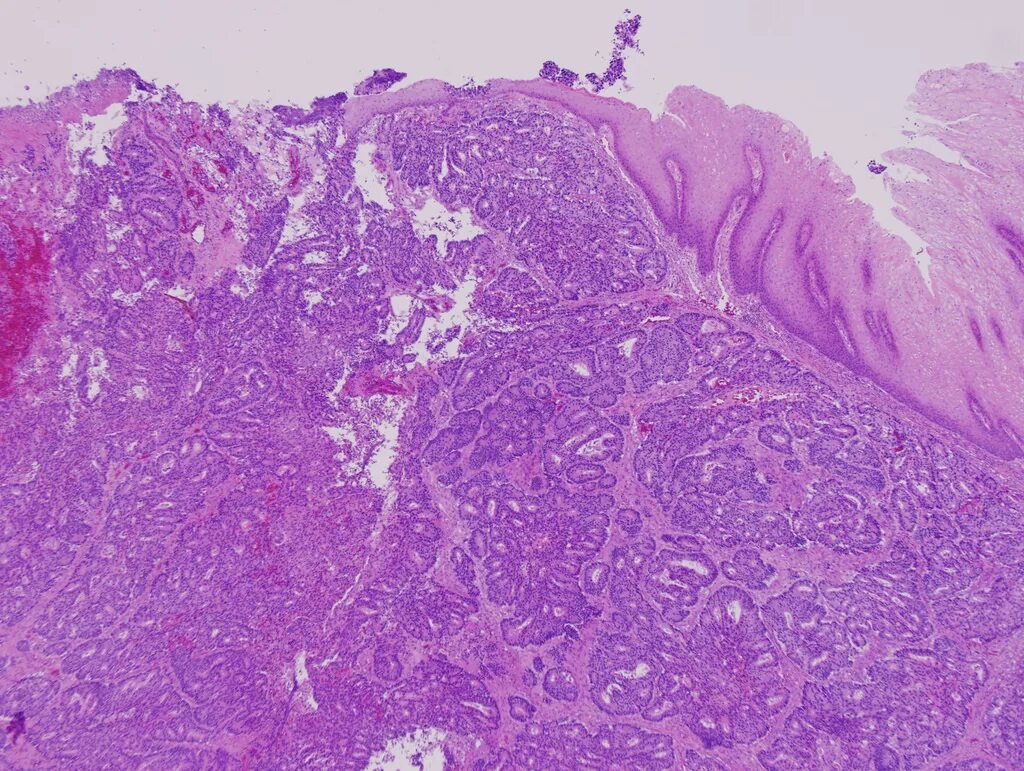

Гистологически аденокарцинома